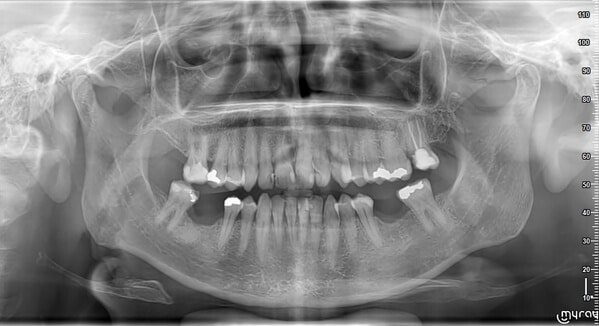

€50Röntgenfoto maken

Maken we een professionele röntgenfoto voor een compleet beeld van uw mondgezondheid

Röntgenfoto

We maken een moderne 2D- of 3D-röntgenfoto voor een compleet beeld. Heeft u al een recente foto? Dan kunt u die ook (liefst digitaal) meebrengen.